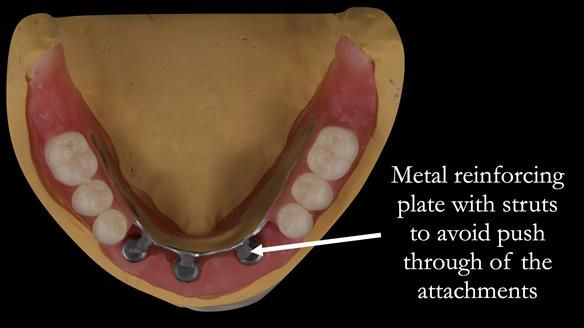

This newsletter describes in step by step detail the provision of a lower implant supported metal based complete denture with three dental implants positioned in the anterior mandible. The upper arch was restored with a metal based complete upper denture.

Mary had 3 dental implants placed in the anterior mandible 10 years previously with new complete dentures. These were successful for a time. The dentures were replaced a few years later. Mary was never pleased with the new lower denture as they did not fit the implants properly. This patient was referred to me from Ireland, to my practice in Garstang, England.

I provided new metal based complete dentures. The clinical situation and treatment process is shown in detail below with photographs. I provided the clinical work and Rowan Garstang provided the technical work. The dentures took 5 visits to make - with the patient travelling by plane from Ireland to Manchester. The patient had one review after the dentures were fitting.